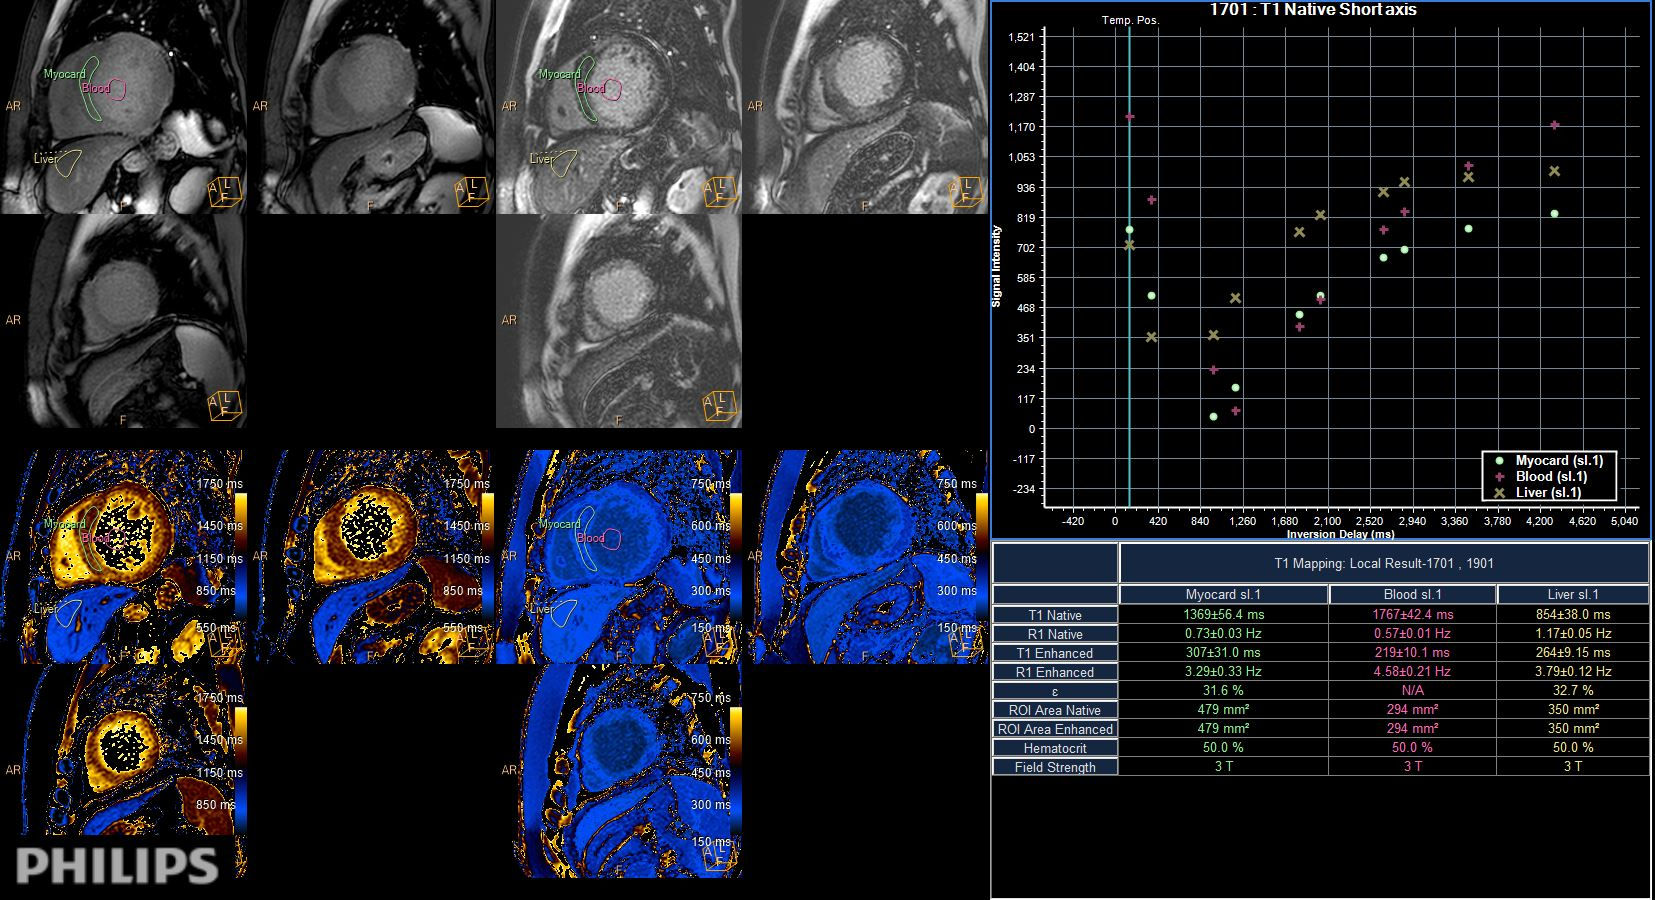

Short axis view (T1 Mapping on ISP 12)